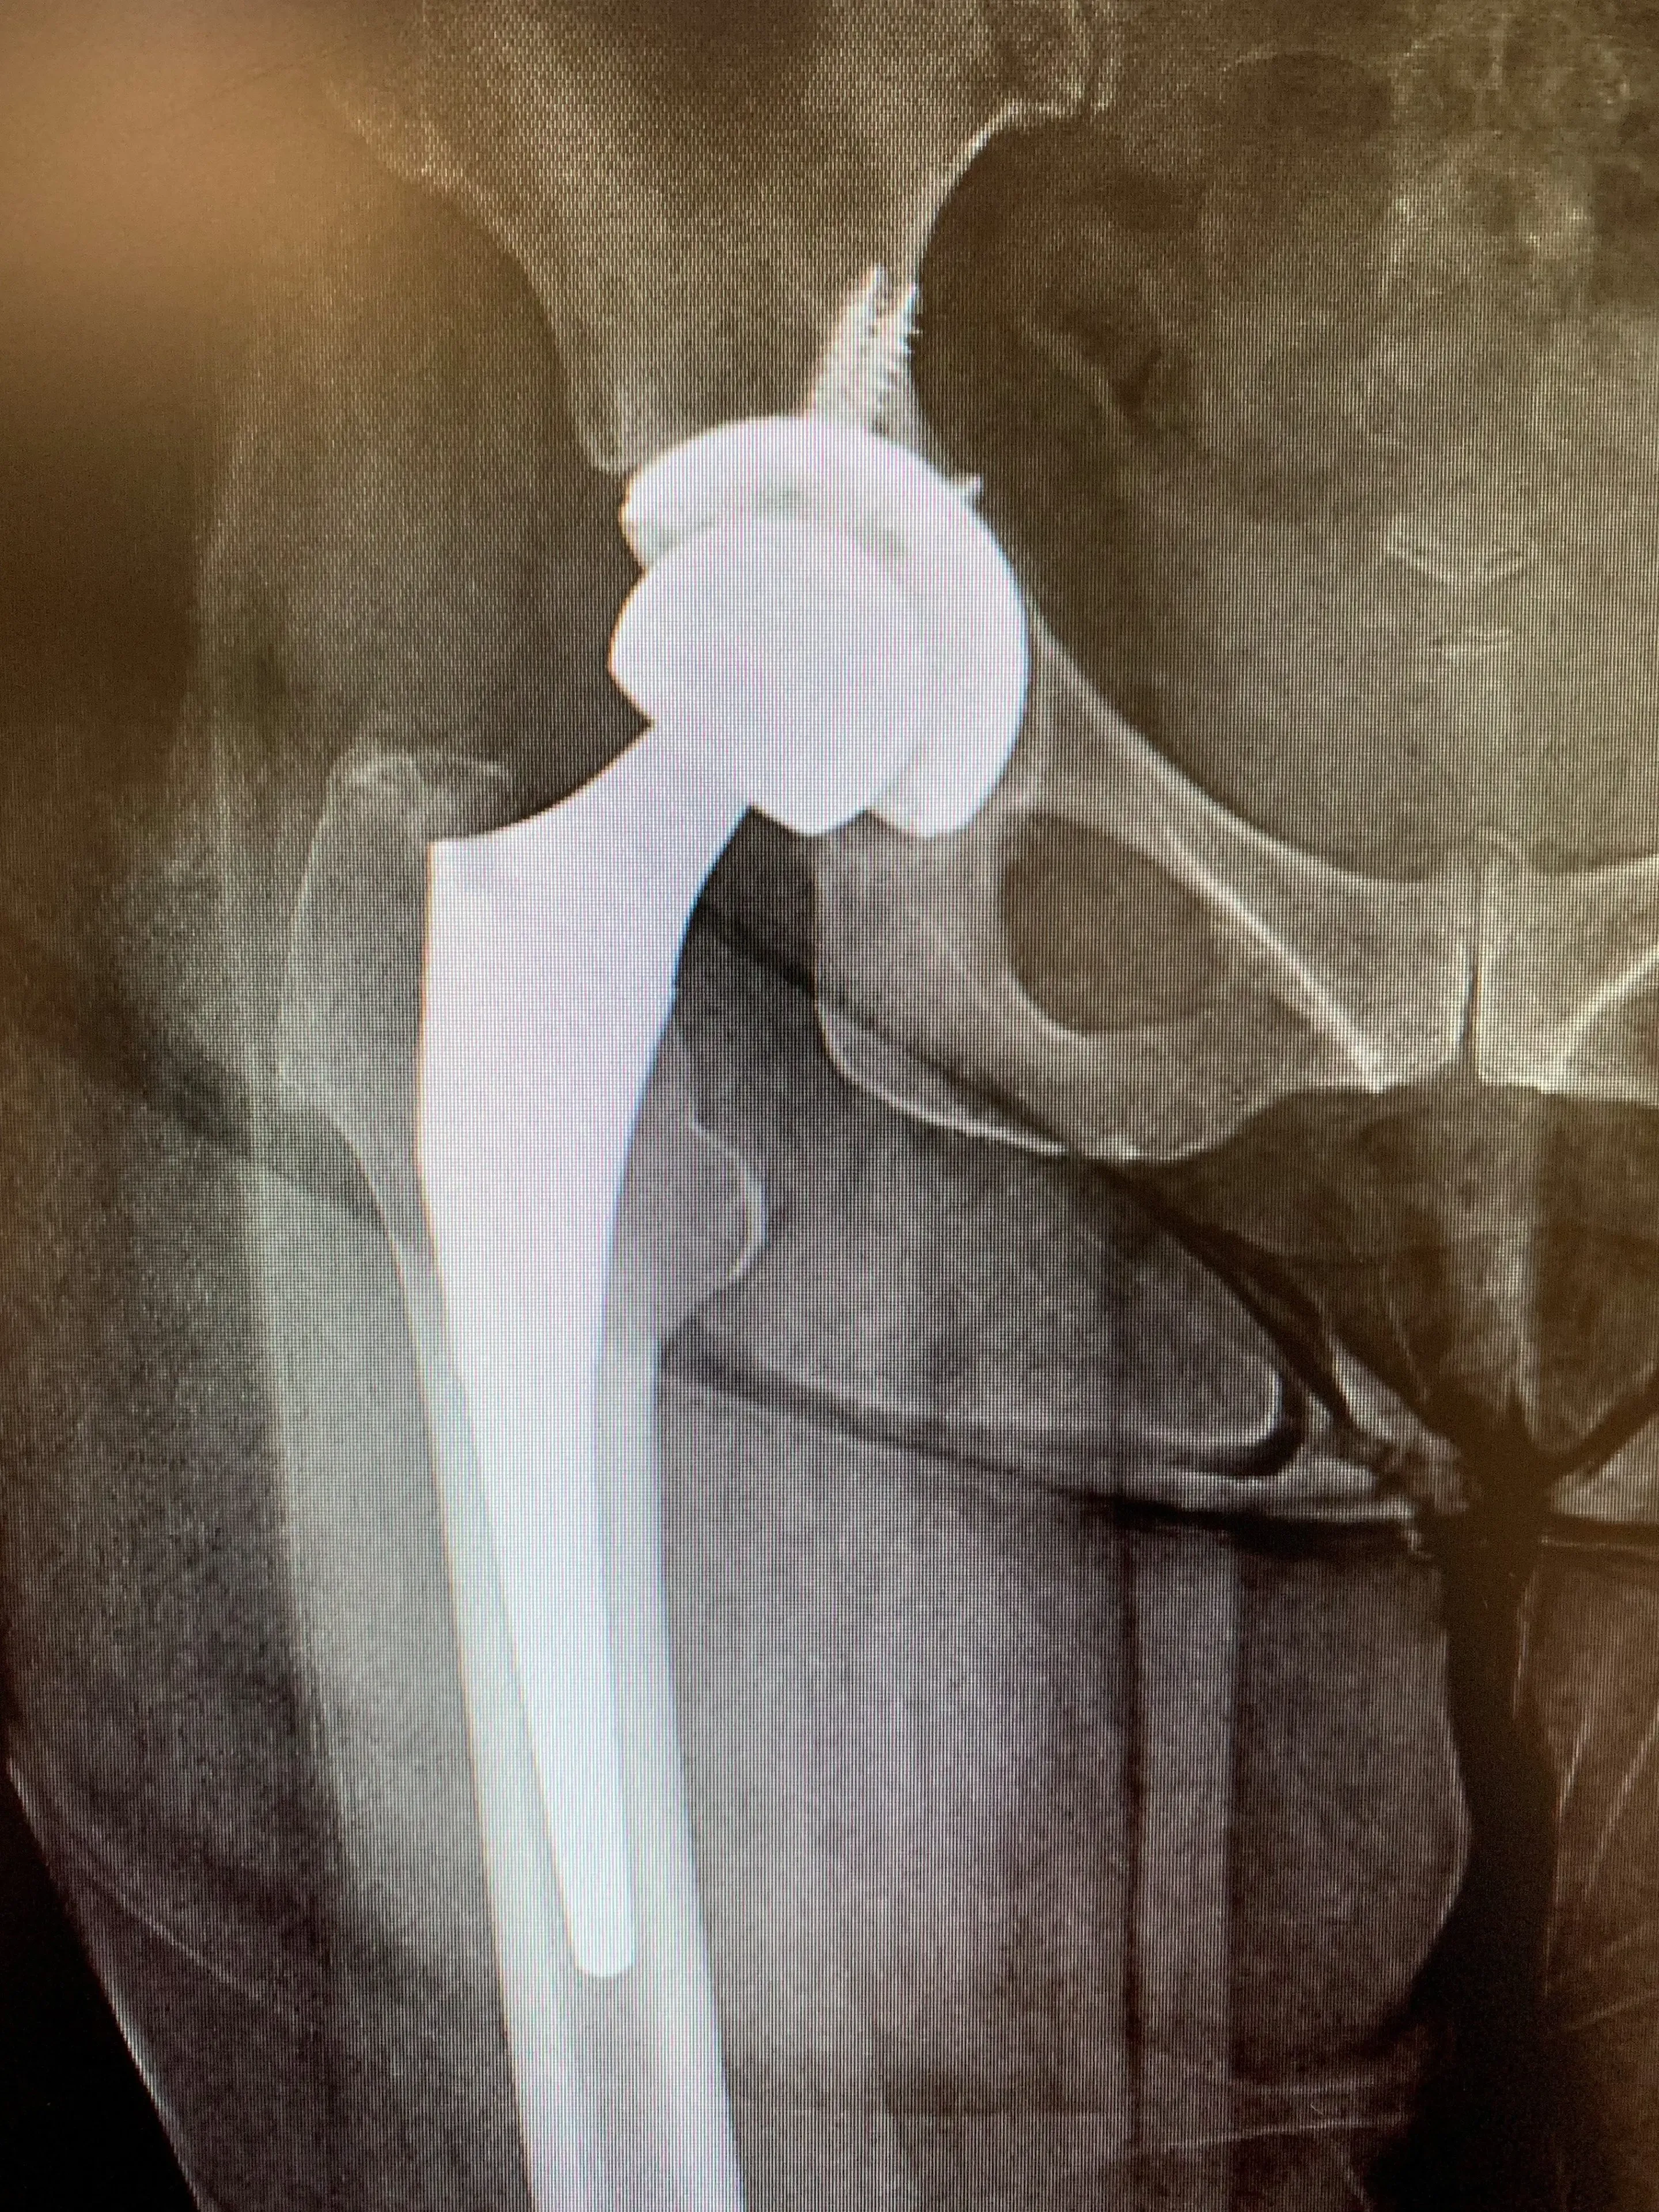

She accepted and consented, and we planned for her to receive surgery as soon as possible. We performed a posterior approach – the approach used for her first hip replacement and exposed her artificial hip fully. We dislocated it and used special instruments to first remove her acetabular liner, and then her acetabular component. We observed minimal bone loss, and so placed a slightly larger revision acetabular component in its place, ensuring stability and leg length were both restored.

Mrs. IS recovered within 3 months of her surgery, and is back to being fit and active and pain-free in her right hip.

Revision total hip replacement in a 64-year-old. Isolated acetabular component exchange.